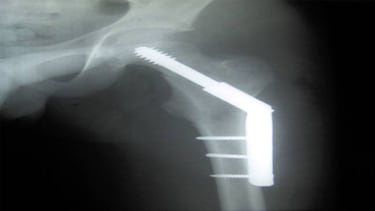

Como todos sabemos el calcio es uno de los componentes de la materia ósea. Pero a la hora de imprimir huesos en 3D se ha utilizado la hidoxiapatita, un material con el que se fabrican las cirugías de reconstrucción. Los investigadores a cargo de este proyecto le añadieron un polímero para darle mayor flexibilidad y fuese más fácil moldearlo.

Entre sus características destaca su capacidad para amoldarse al espacio. Se puede cortar, aplastar y doblar sin esfuerzo, pero lo que más llama la atención es que no necesita pegamento ni puntos de sutura para unirse a la parte dañada o que va a remplazar. Por su fuera poco, favorece al crecimiento de vasos sanguíneos gracias a que es un material absorbente y poroso.